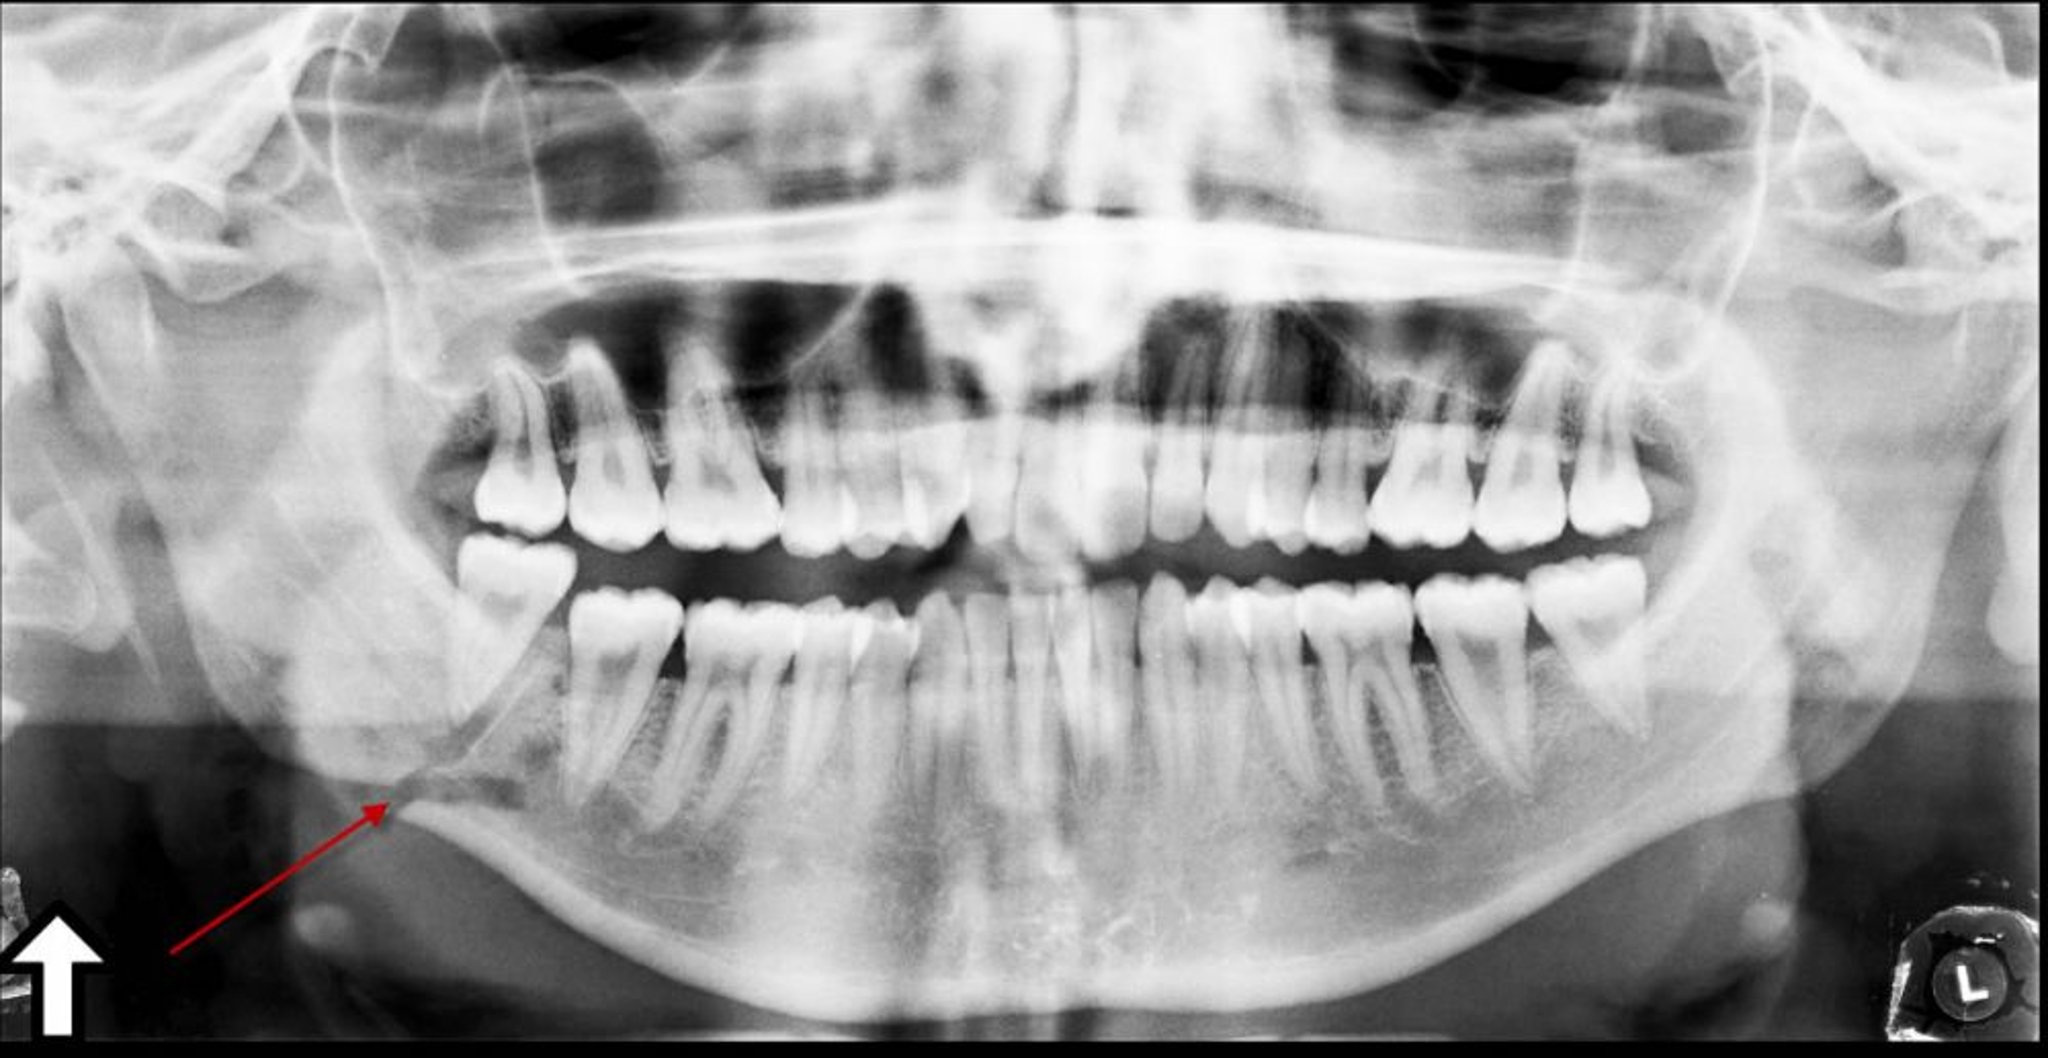

Перелом угла нижней челюсти

Эта панорамная рентгенонрамма показывает просветление (стрелка) под углом нижней челюсти, представляющие собой перелом.